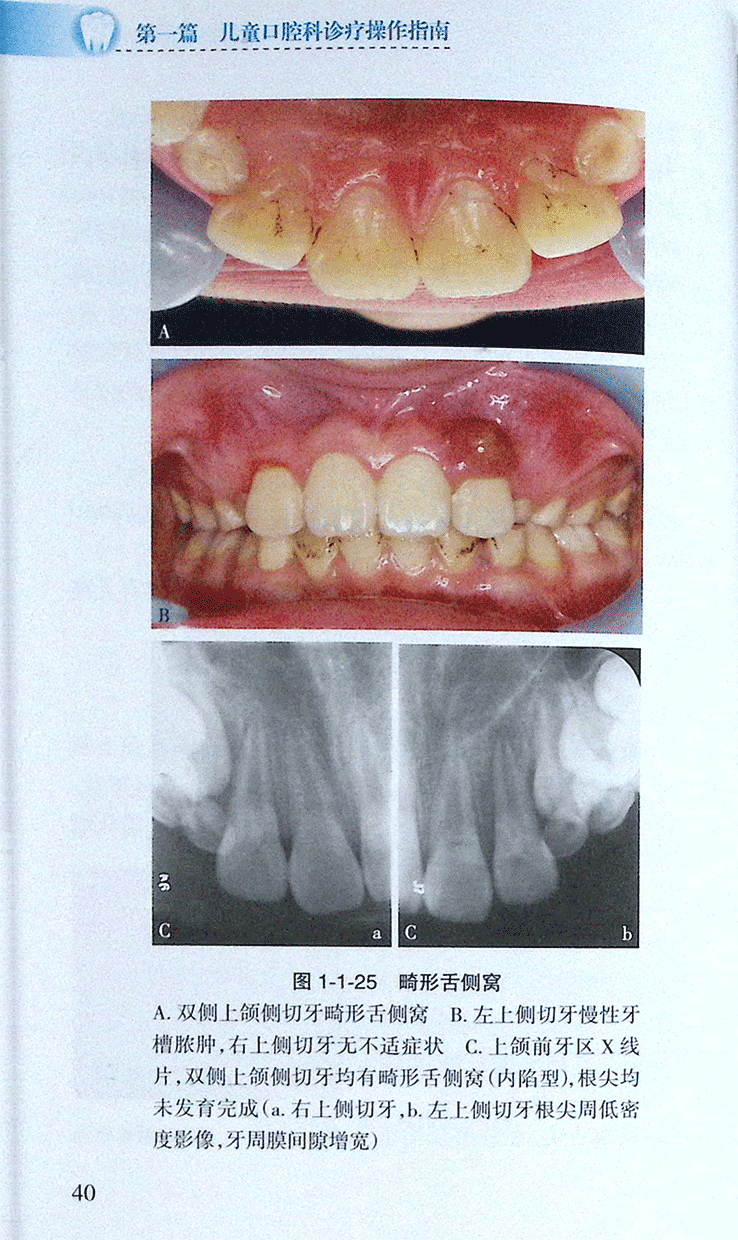

>>(四)畸形舌窝、畸形舌尖